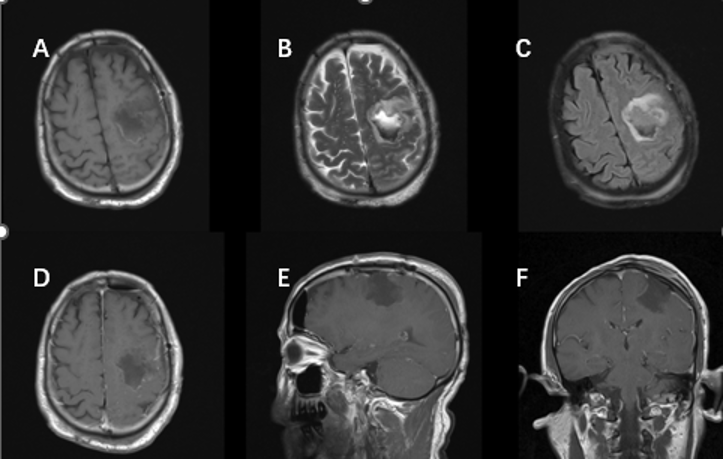

完善术前准备,排除手术禁忌后,患者于2019年3月行黄荧光引导下左侧额叶肿瘤切除术+硬膜修补+颅骨成形术。术中标记左侧额颞顶部马蹄形切口,游离骨瓣,剪开硬膜翻向中线。显微镜下沿肿瘤皮层造瘘,见肿瘤呈灰红色、质地稀软、血运差、边界清晰,沿囊壁完整切除肿瘤,达显微镜下全切除。术后患者恢复顺利,未见神经功能症状加重。术后常规复查头颅增强MRI提示肿瘤全切(图2)。

图2.术后头颅MRI增强扫描显示肿瘤全部切除